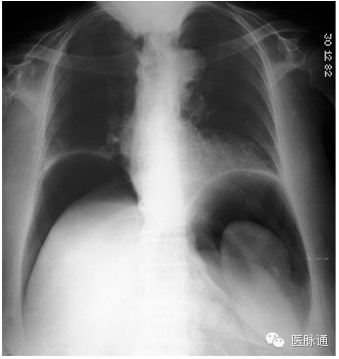

图1是1例具有大量气腹的患者,肝和脾的轮廓清晰可见。

图1